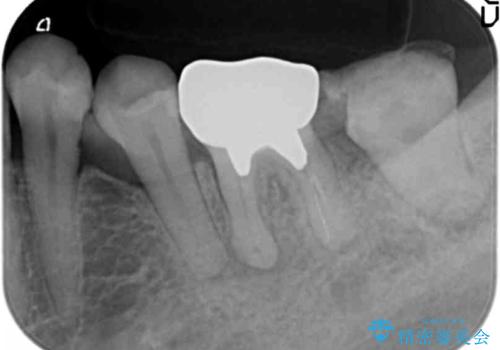

左下の奥歯(左下7)は破折しており保存不可能な状態でした。

ご希望により、隣の親知らず(左下8)を移植しました。

移植後、生着を待って根管治療及び補綴修復を行いました。

※術前にレントゲン・CTを撮影し、抜去する歯と親知らずの根の長さ・幅径・形態を確認し、移植の可否を判断してから手術を行っております。